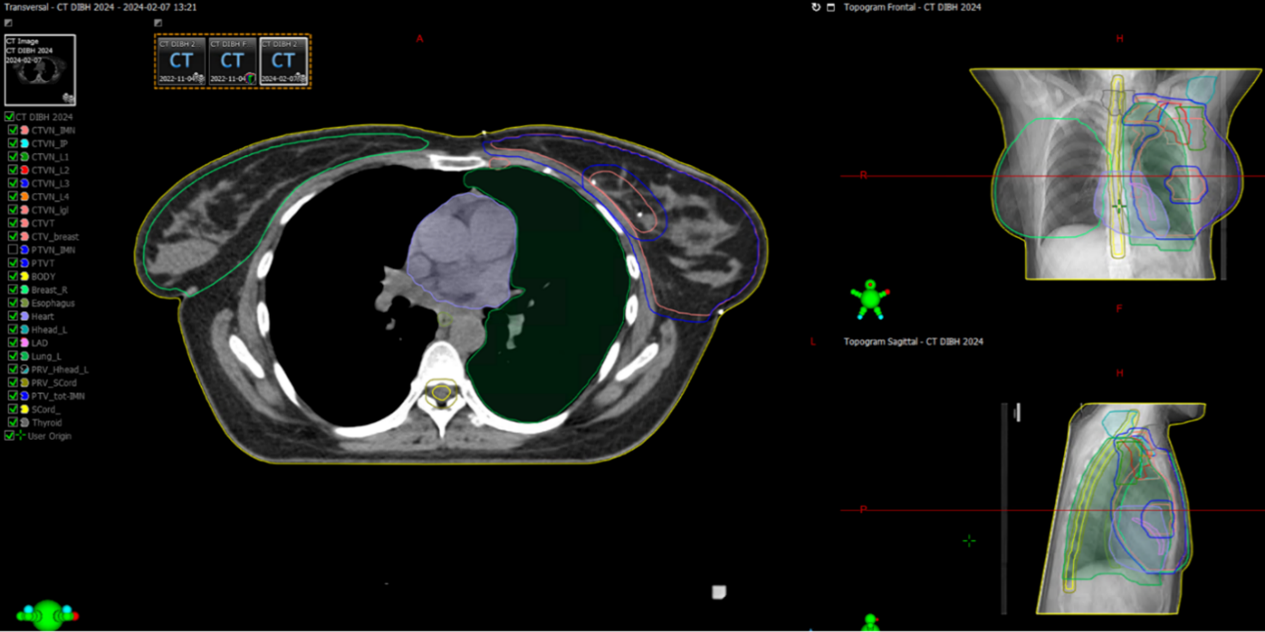

Figur 1. Exempel med CTVT, PTVT, CTV bröstkörtelvävnad och lymfkörtlar med PTV inritat.

Figur 2. CTV enligt ESTRO consensus guideline [4]. Targetvolymen innehåller all bröstkörtelvävnad. Röntgentät tråd kan användas vid CT-undersökningen för att markera kvarvarande bröst, ärr efter sektorresektion/mastektomi eller området där bröstet suttit efter mastektomi.

Figur 3. CTVN enligt ESTRO consenus guideline [4]. Inritningen av lymfkörtelvolymerna underlättas genom att vissa landmärken i form av vener och artärer definieras.